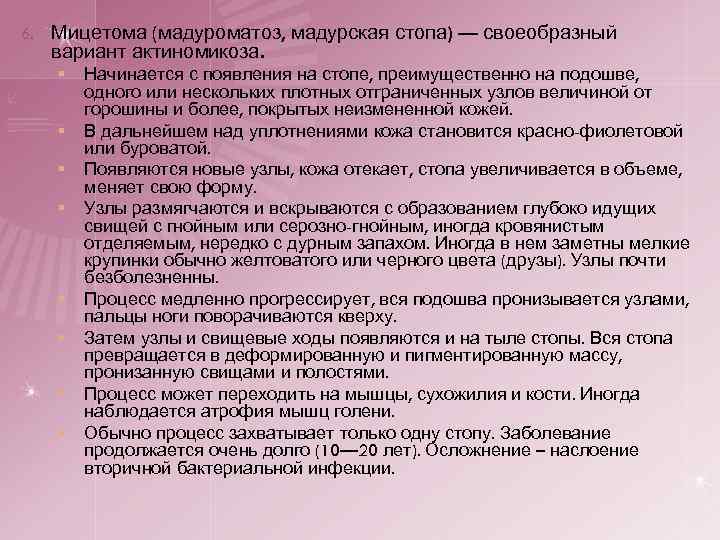

6. Мицетома (мадуроматоз, мадурская стопа) — своеобразный вариант актиномикоза. § § § § Начинается с появления на стопе, преимущественно на подошве, одного или нескольких плотных отграниченных узлов величиной от горошины и более, покрытых неизмененной кожей. В дальнейшем над уплотнениями кожа становится красно-фиолетовой или буроватой. Появляются новые узлы, кожа отекает, стопа увеличивается в объеме, меняет свою форму. Узлы размягчаются и вскрываются с образованием глубоко идущих свищей с гнойным или серозно-гнойным, иногда кровянистым отделяемым, нередко с дурным запахом. Иногда в нем заметны мелкие крупинки обычно желтоватого или черного цвета (друзы). Узлы почти безболезненны. Процесс медленно прогрессирует, вся подошва пронизывается узлами, пальцы ноги поворачиваются кверху. Затем узлы и свищевые ходы появляются и на тыле стопы. Вся стопа превращается в деформированную и пигментированную массу, пронизанную свищами и полостями. Процесс может переходить на мышцы, сухожилия и кости. Иногда наблюдается атрофия мышц голени. Обычно процесс захватывает только одну стопу. Заболевание продолжается очень долго (10— 20 лет). Осложнение – наслоение вторичной бактериальной инфекции.

Рис. 12 Мадурская стопа